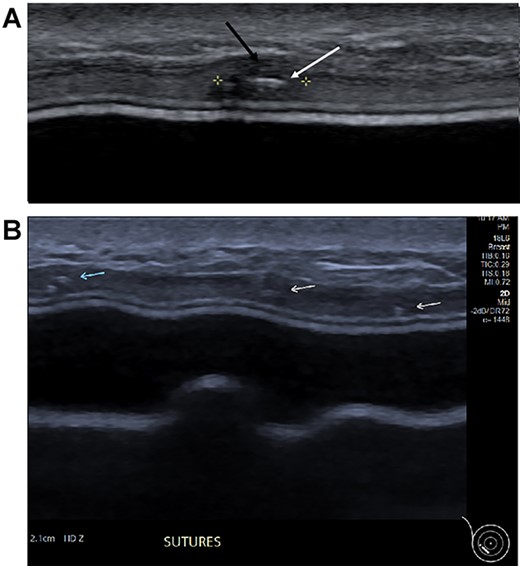

Three months postoperatively, the patient presented to the breast clinic with a nodule on the lower part of her left reconstructed breast deep to her (wide excision) scar. Ultrasound revealed an indeterminate nodule with a bright echoic centre. Differentials included the unabsorbed knot of an internal suture or possible local recurrence. Dynamic contrast breast MRI, however, did not demonstrate any abnormal enhancement. Ultrasound undertaken along with the operating surgeon demonstrated the patch of ADM inserted at the time of initial surgery as a thickening, with three identical regularly placed nodules measuring 3–5 mm corresponding to PDS sutures (Fig. 4), thus avoiding unnecessary surgery. Four months post-operatively, the nodule was no longer palpable.

(A) Magnified ultrasound image identified a 5 mm hypoechoic focus of thickening within the capsule (black arrow and area between the cursers) with two parallel lines centrally within the focus which represents the suture (white arrow). (B). The ultrasound demonstrates the equally placed sutures identified as small white parallel lines (arrows) across the ADM.

This case report also highlights the challenges in the diagnosis of lesions that are closely associated with implants. MRI interpretation can be challenging when differentiating between local recurrence and postoperative changes such as granulomas associated with sutures as both can have enhancement including type 1 kinetics [10, 11]. This can be a particular problem when non-absorbable or long-lasting sutures are used, which is demonstrated in a previous case report describing sutures masquerading as a breast lesion [12]. MRI is beneficial in identifying the extent of disease for surgical planning.

Ultrasound can demonstrate excellent views of the implant [13]. It is important for the radiologist to fully understand the surgical techniques involved in cases of breast reconstruction and to bear in mind suture position when reporting the images. It is incumbent on surgeons to give the radiologists adequate information as to the previous surgical procedures and highlight any differential diagnoses to them in the radiology request.